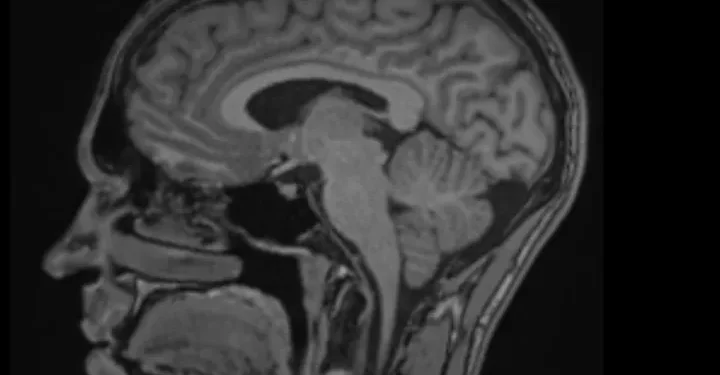

Imagen de la campaña de Go Fund Me.

Un joven de 21 años residente en Ibiza ha iniciado una campaña solidaria a través de la plataforma GoFundMe con el objetivo de recaudar 14.000 euros que le permitan someterse a una intervención quirúrgica especializada. Según informa a través de la plataforma, padece una malformación de Chiari y un quiste aracnoideo cerebral que le provocan «dolor crónico, cefaleas persistentes, pitidos en los oídos, alteraciones visuales, fasciculaciones y dificultades para concentrarse».

El joven comenzó a experimentar estos síntomas hace cuatro años, cuando una cefalea común evolucionó hacia un cuadro neurológico complejo que no ha remitido a pesar de múltiples tratamientos y consultas médicas. Ante la falta de resultados en el sistema público, optó por buscar atención en el ámbito privado, donde un neurocirujano especializado identificó la malformación y el quiste y propuso una operación como única opción para aliviar los síntomas.

La cirugía consiste en reconstruir la fosa posterior del cráneo, extirpar el quiste y ampliar el espacio suboccipital para mejorar el flujo del líquido cefalorraquídeo y reducir la presión sobre el cerebelo. El procedimiento, considerado de alta complejidad, tiene un coste total que incluye honorarios médicos, hospitalización, materiales quirúrgicos y seguro.